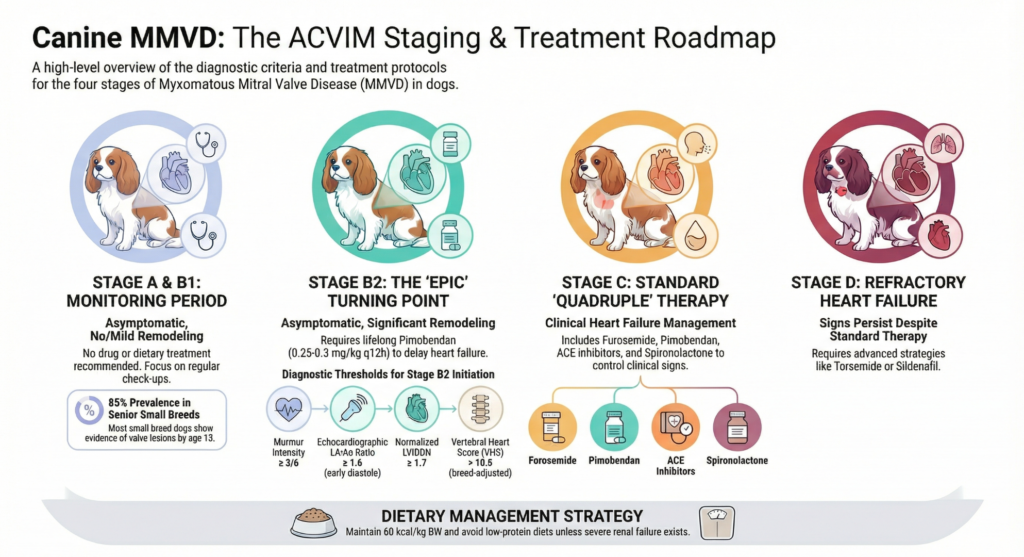

What are the stages for MMVD?

- Stage A: Dogs at high risk (e.g., Cavalier King Charles Spaniels, Poodles) with no current murmur.

- Stage B: Dogs with a murmur but no clinical signs of heart failure.

- B1: No or minimal heart enlargement; treatment is not yet required.

- B2: Significant heart enlargement; treatment is started here to delay the onset of heart failure.

- Stage C: Dogs with current or past signs of heart failure (e.g., fluid in the lungs).

- Stage D: End-stage disease where clinical signs no longer respond well to standard treatment.